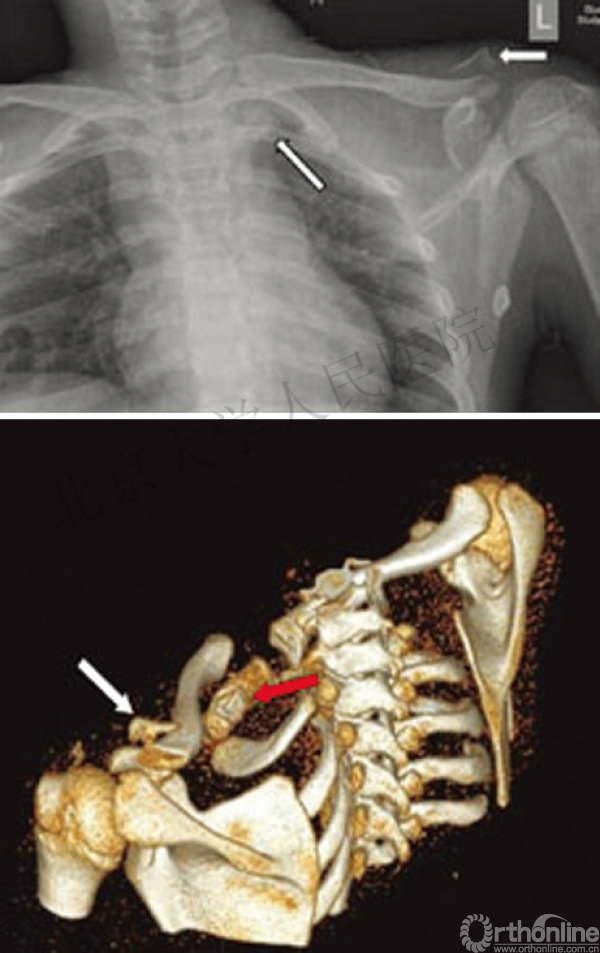

43岁男性,骑电动车时发生交通事故摔伤左肩及左胸

查体:左胸壁后方压痛;左锁骨近端区域凸起,压痛(+),远端未见明显畸形,压痛(+),锁骨轴向叩痛(+)

影像学检查—X线

你是否认为容易漏诊?

影像学检查—CT平扫

影像学检查—CT三维重建

1.创伤性漂浮锁骨(左侧)

(1)锁骨远端骨折

(2)锁骨近端骨折

(3)胸锁关节脱位

2.左侧肋骨骨折(2-3后肋)

3.软组织损伤(左肩部及胸壁)